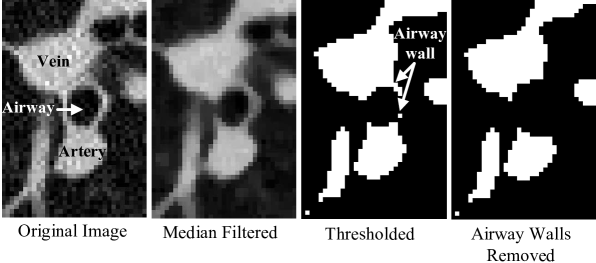

3.2 Vessel tracking

Of the 20 arterial trees to be segmented across the ten cases (10 left and 10 right arterial trees), 19 were successfully seeded as the arteries entered the lungs. The vessel trackers stemming from the automated seed point segmented a total of 134 of the 210 manually identified arteries to within an RMS distance error of less than 2.0 mm, yielding an overall sensitivity of 64%. 20 of 205 veins were erroneously segmented as arteries, yielding an overall specificity for artery segmentation of 90%. Figure 7 shows the segmentation results, both overlaid on an axial CT slice and as a 3D surface representation.

Figure 8 shows the results of the weakest and strongest segmentations, overlaid with truth markings for the arteries. In the case of the strong segmentation, the algorithm was able to correctly seed the pulmonary artery, and separate and segment the arterial tree to four generations. Additionally, the true vessel surface matched the segmented surface very closely. In the case of the weak segmentation, a segmental child branch failed to be detected, which resulted in several missed arteries. The vessel tracker also leaked onto the adjacent venous tree, returning false-positives (non-arteries).

Refer to caption

Figure 7: a) Axial slice from a section of the inferior lung. Vessels in red indicate the segmentation result. b) Three dimensional rendering of the pulmonary arterial tree generated by our automated method.